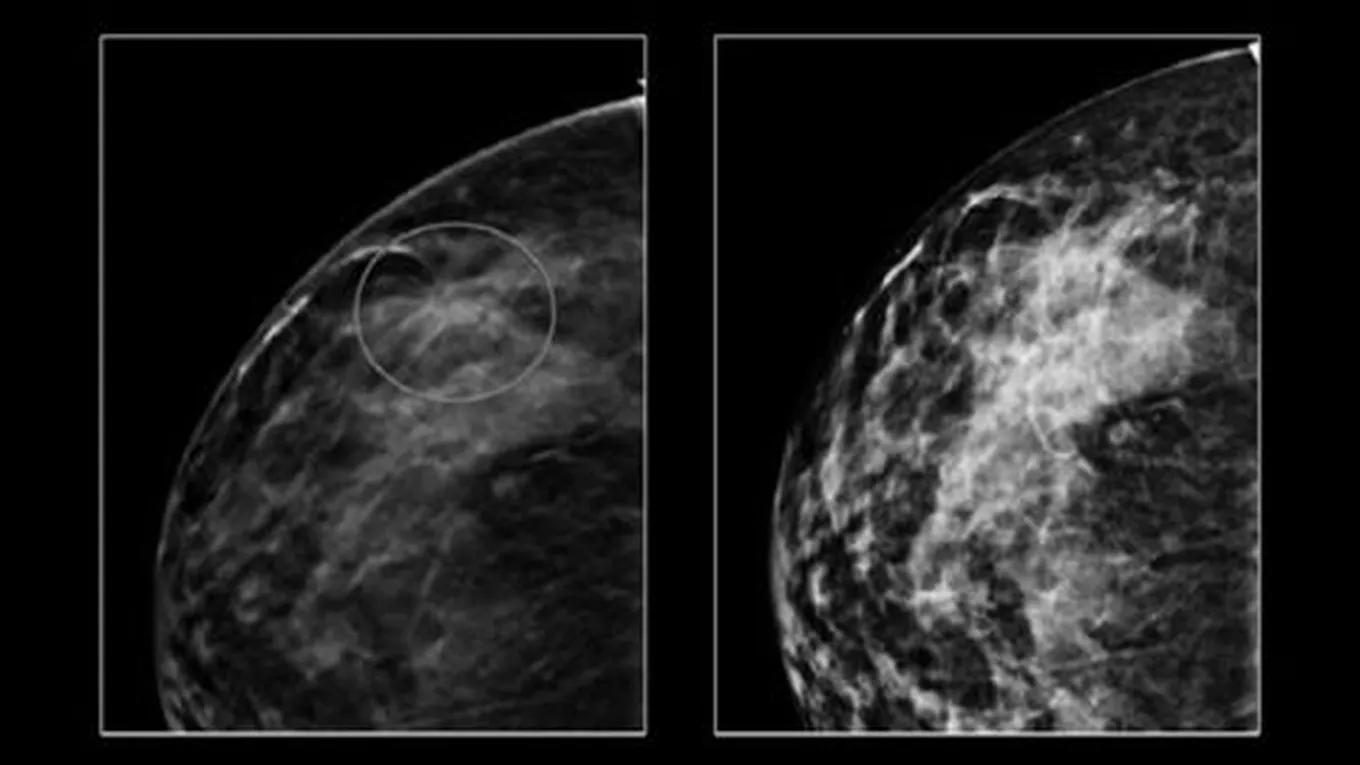

- عمل صورة أشعة للثدي كل سنتين، وبعد الوصول إلى عمر الأربعين فيُفضّل عملها سنوياً.